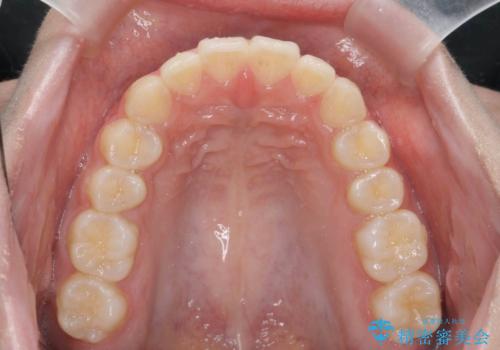

ワイヤー、マウスピースにはそれぞれ得意な動き、不得意な動きがあります。

長所・短所をうまく使い分けることで矯正治療の期間を短縮することができます。